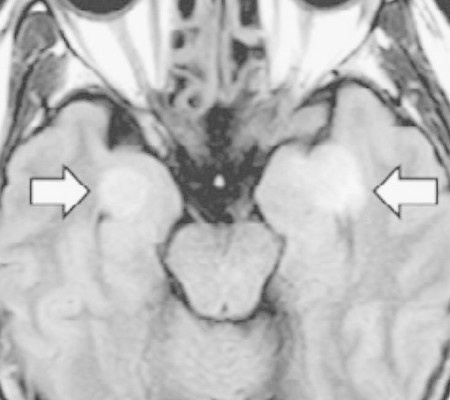

A ciência ainda não desvendou como o coronavírus pode atacar o cérebro. Mas chamou atenção o caso de uma funcionária de uma companhia área nos EUA de 58 anos, sem comorbidades. Com diagnóstico de Covid-19, ela desenvolveu encefalopatia aguda necrotizante, uma doença rara e gravíssima.

Ela teve sintomas como desorientação e perda de memória em apenas três dias. O caso foi descrito na revista médica Radiology. A mulher sobreviveu, mas não se sabe se terá sequelas.